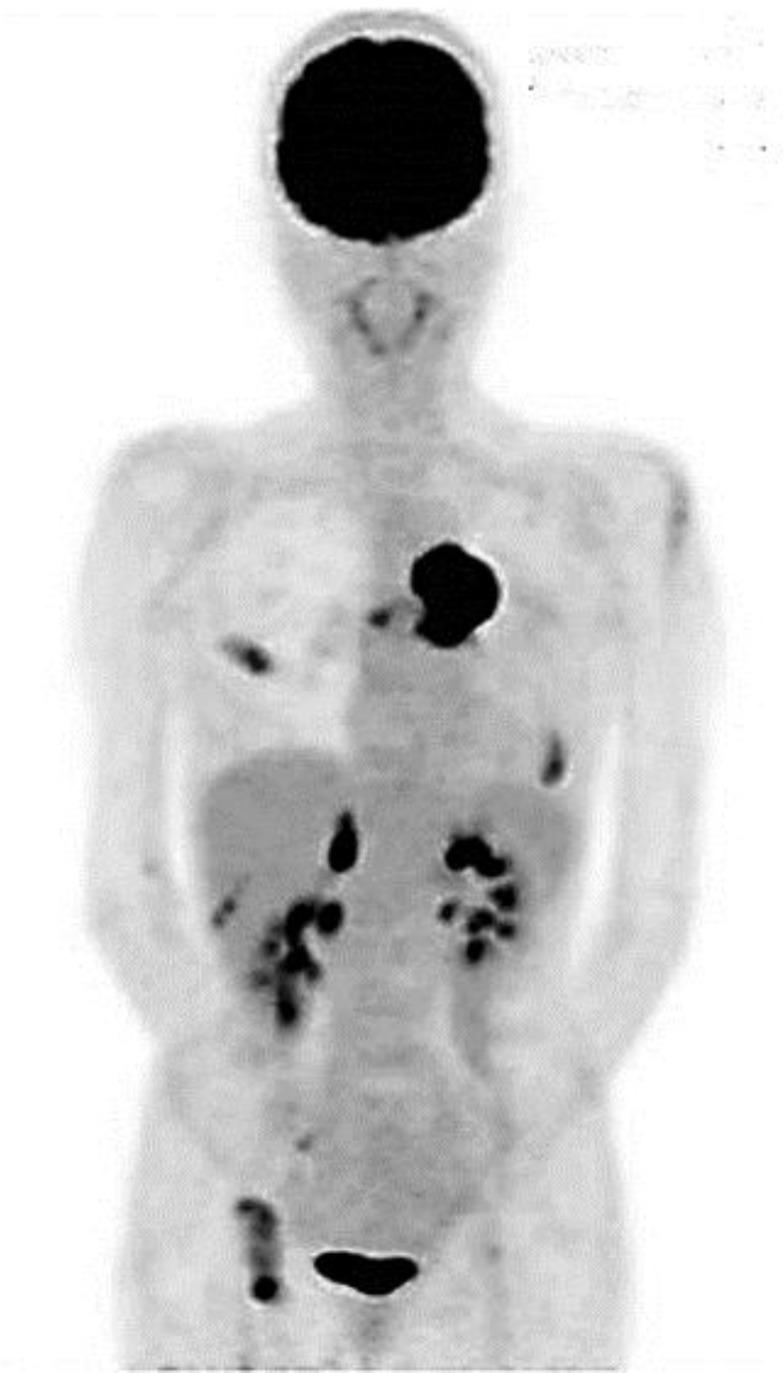

Undifferentiated malignant neoplasms, which occur primarily in the pulmonary artery, are extremely rare and associated with poor outcomes as there is no effective therapy. A 67-year-old woman visited our hospital with complaints of dry cough and dyspnea on exertion. A contrast-enhanced chest computed tomography revealed an intravascular tumor obstructing the left pulmonary artery and a pedunculated lesion extending to the main and right pulmonary artery. Multiple metastases in the lung, bones and bilateral adrenal glands were identified by fluorodeoxyglucose-positron emission tomography. A small sample was obtained by catheter aspiration biopsy of the intravascular tumor, and examination revealed undifferentiated small atypical cells. The tumor was diagnosed as an undifferentiated neoplasm arising from the pulmonary artery based on immunohistochemical findings, including the absence of expressions of organ-specific markers. Systemic chemotherapy (paclitaxel and carboplatin) and concurrent radiation were performed as treatment for the primary tumor. Marked shrinkage of the intravascular tumor was achieved, and no serious adverse events were observed during therapy. Chemotherapy was continued for 5 months, but the patient died because of tumor progression 9 months after the initial diagnosis. Chemoradiotherapy has efficacy against undifferentiated neoplasm of the pulmonary artery.